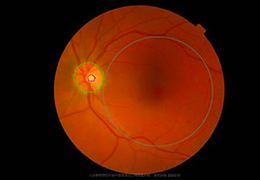

成像智能。

Eclipse 成像智能功能提供强大的处理能力和最佳质量的影像,同时减少质量错误并提高剂量效率。

凭借 AI、专有算法和先进的影像处理能力,提供出色的影像质量和无与伦比的诊断信心。